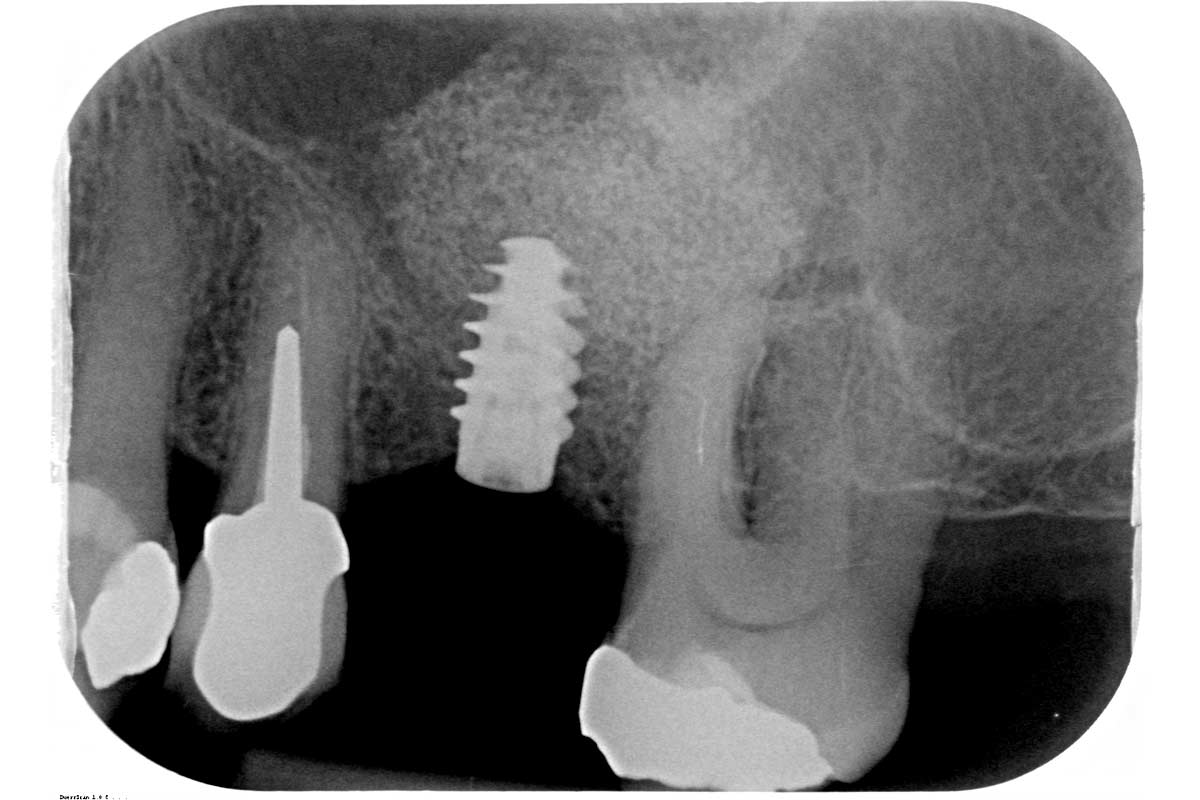

01/35 - Initial x-ray, tooth 25 compromised and to be extractedMaxillary sinus cyst removal using the Crocodile Technique and subsequent lateral sinus lift - Dres. C. Scognamiglio and A. Perucchi